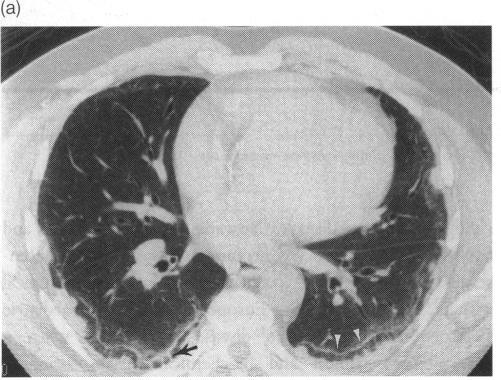

Woodard P K, McAdams H P, Putman C E

Department of Radiology, Duke University Medical Center, Durham, North Carolina 27710, USA.

J R Soc Med. 1995 Dec;88(12):669-71. doi: 10.1177/014107689508801204.